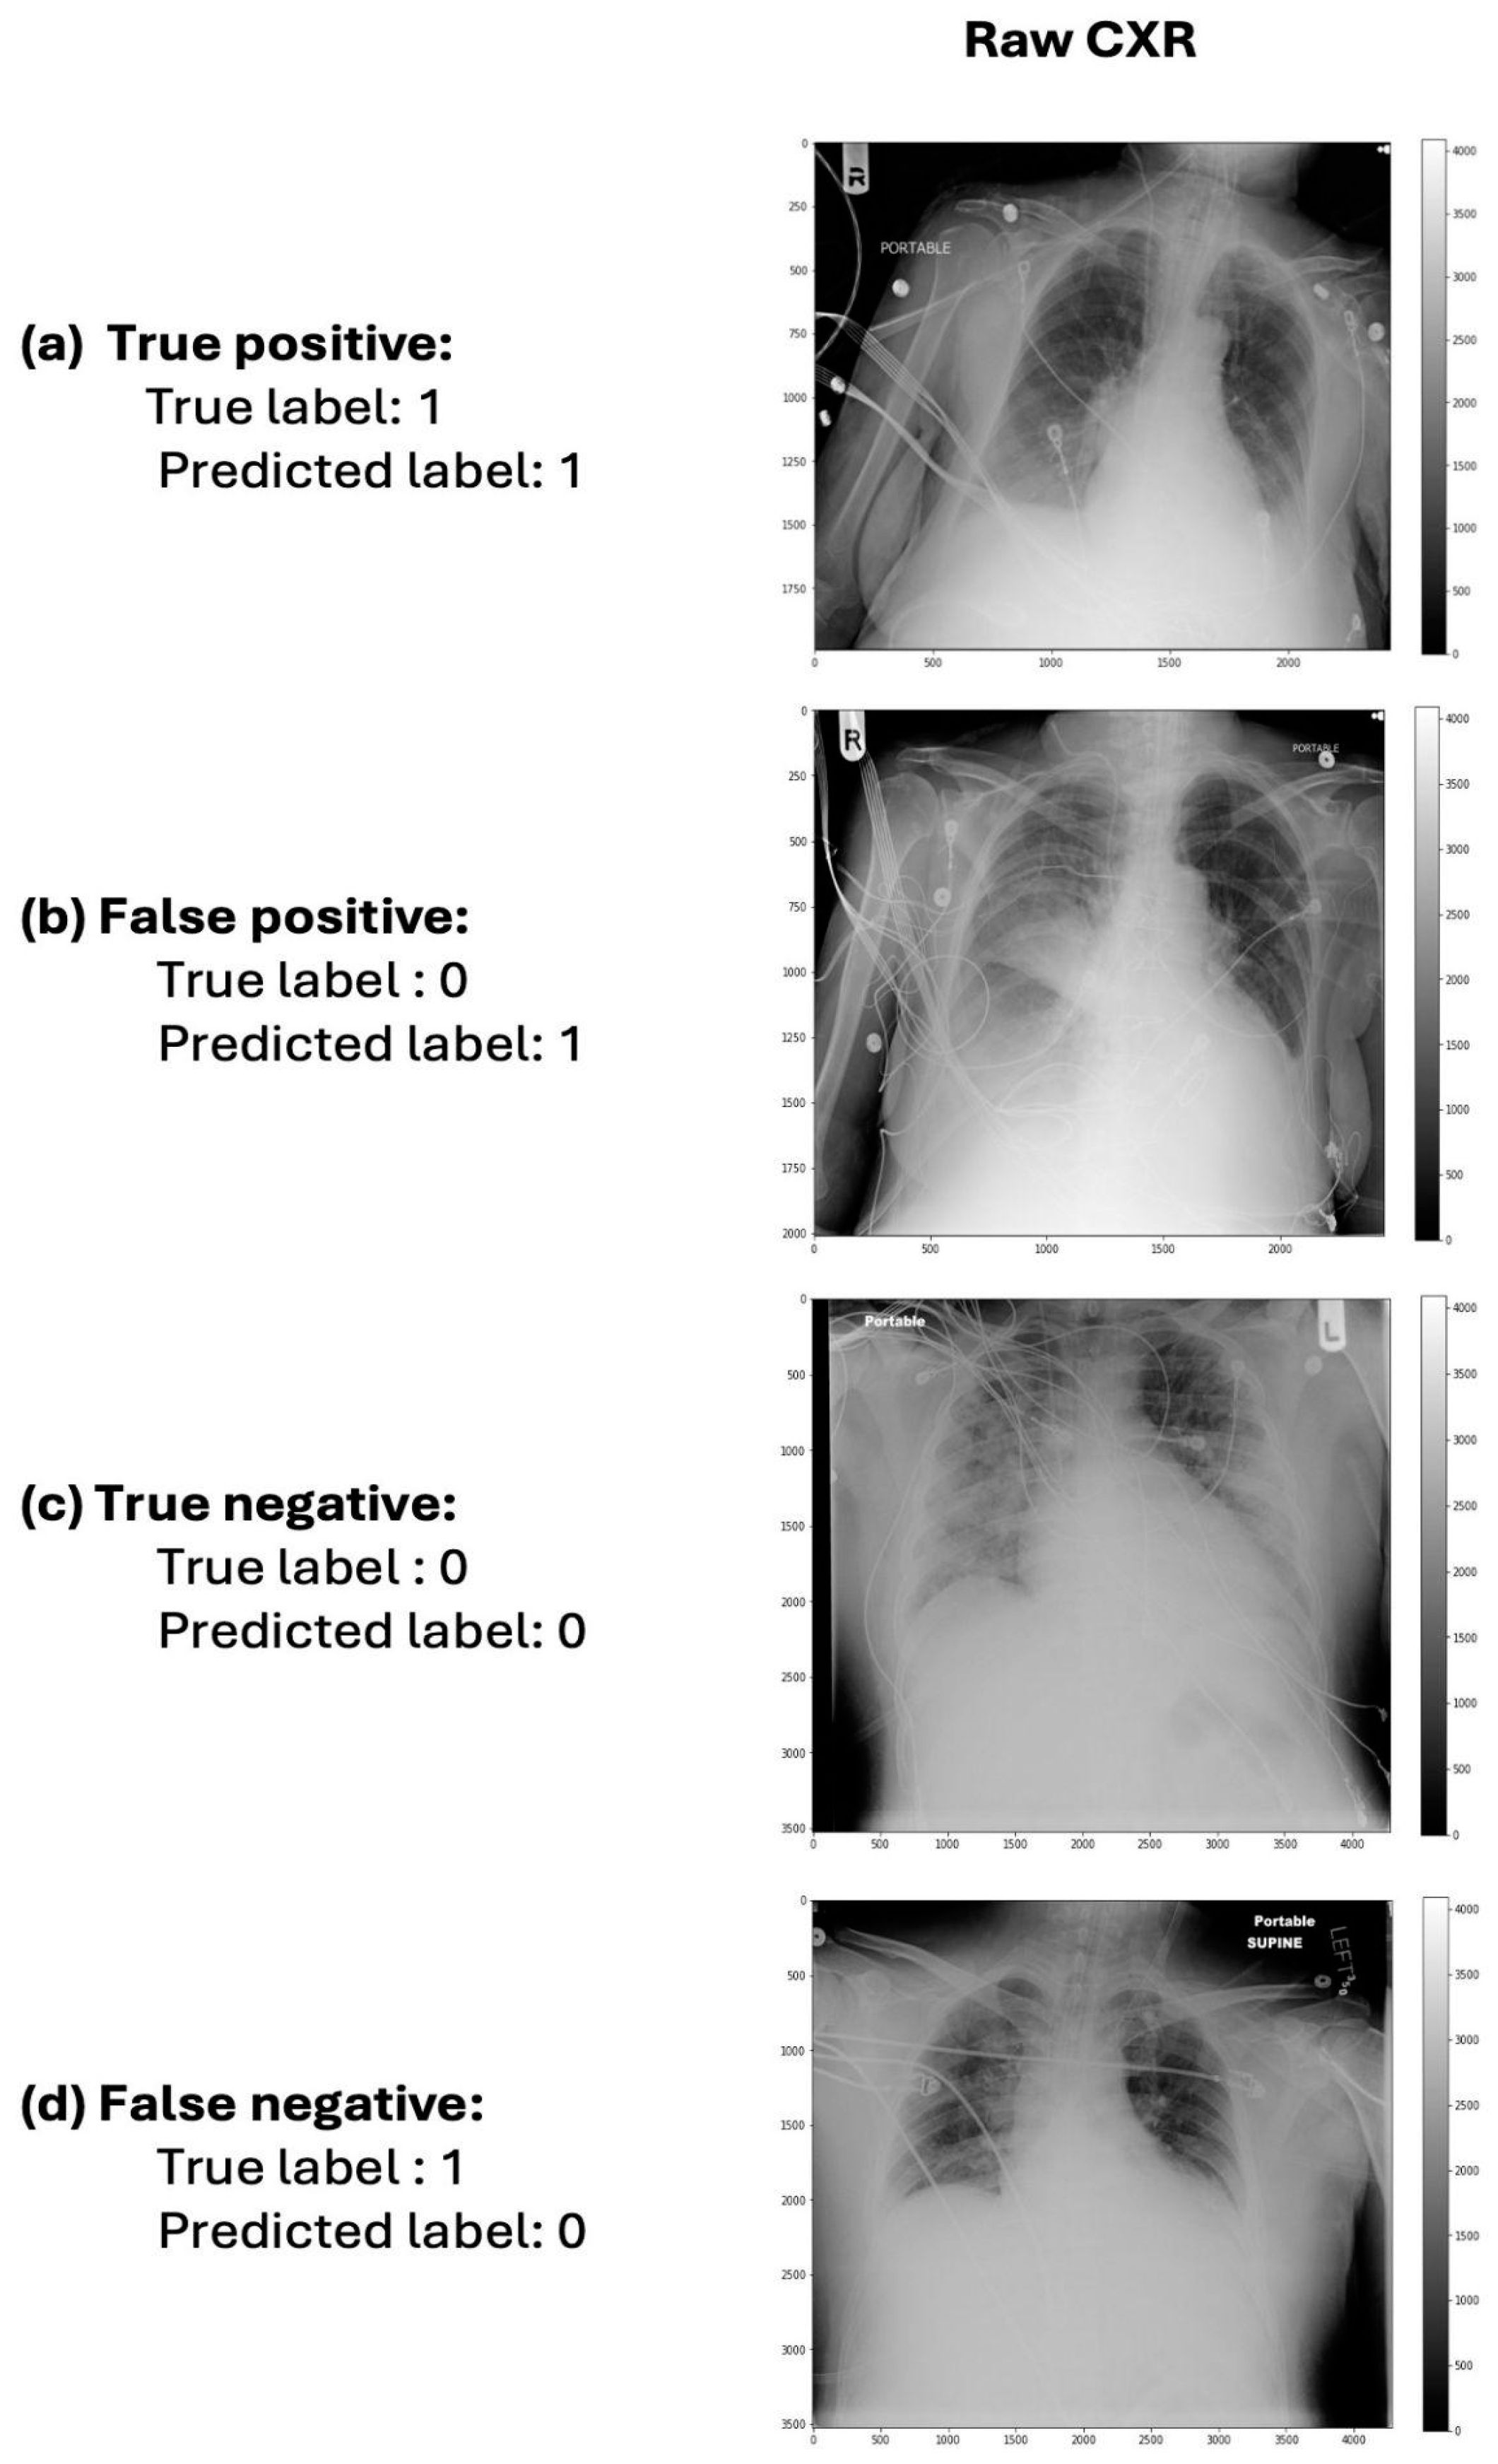

3.2. Final Imaging Classifier and Predictors in the Imaging Classifier